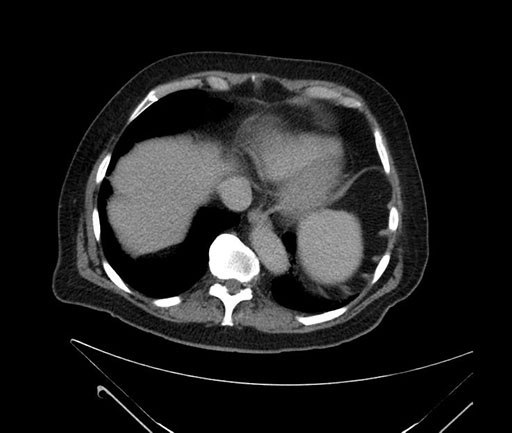

Axial - stented